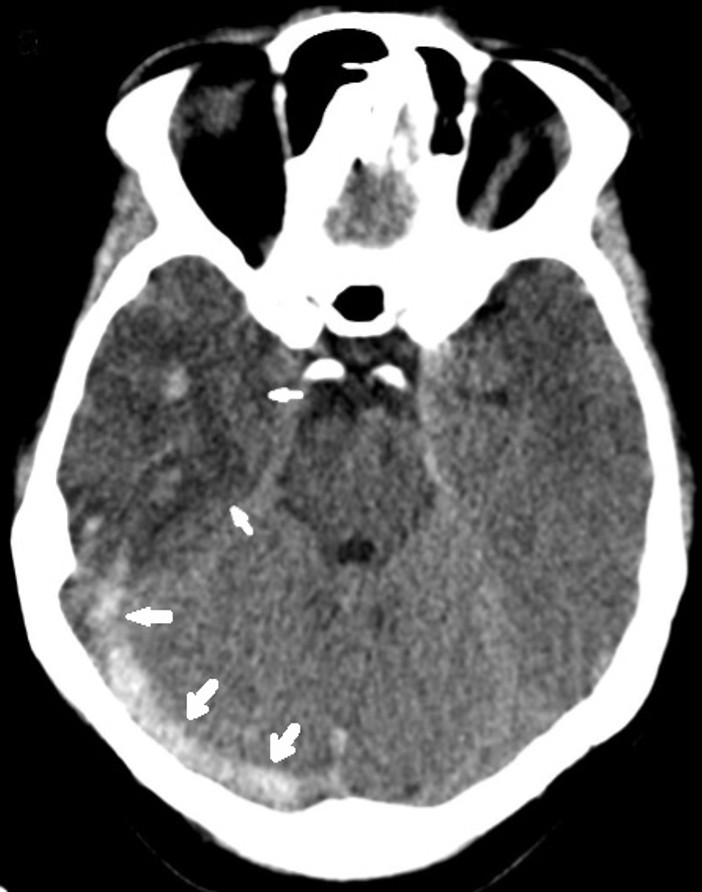

A 17-year-old female patient presented to the emergency department with complaints of severe headache for 1 week and slowed movements and left extremity weakness that started 1 day ago. Physical examination revealed a body mass index of 26 kg/m2, an obese appearance, and signs of hirsutism. In vital signs, blood pressure was 120/75 mmHg, pulse rate was 70 beats/minute, and temperature was 36.7°C. Neurological examination revealed consciousness and central facial paralysis on the right, muscle strength was 2/5 in the left lower and upper extremities, and other system examinations were normal. Glasgow Coma Scale was 10. Papilledema was detected. Laboratory findings included hemoglobin: 10.2 g/dL, MCV: 83.5 fL, platelet count: 13,000/mm3, WBC: 3350/mm3, and absolute neutrophil count: 1750/mm3, sodium: 135, potassium: 3.8, creatinine: 0.68. Prothrombin time: 13 seconds, D-Dimer: 3.3 was high. Brain tomography performed at an external center revealed no pathology. Magnetic resonance imaging (MRI) of the brain performed in our center at his presentation to us with complaints of increased headache and weakness revealed changes compatible with diffuse thrombus in the right transverse sinus, sigmoid sinus and jugular vein (Figure 1), signal increase and oedema compatible with venous hemorrhagic ischemia in the supratentorial right temporal, right basal ganglia and thalamic region (Figure 2), and changes suggestive of right to left shifting and uncal herniation. When her history was questioned, it was learnt that she had no previous thrombosis and no known systemic disease, and she had been using OCS containing 0.02 mg ethinylestradiol and 3 mg drospirenone for 1 year due to oligomenorrhoea. The patient underwent anterior temporal lobectomy and thrombectomy with urgent surgical decompression due to diffuse thrombus, shifting, and herniation findings, and altered consciousness on brain MRI (Figure 2)